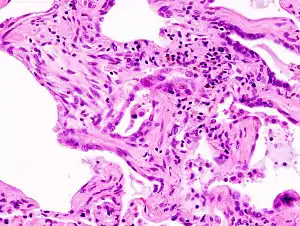

| End-stage pulmonary fibrosis of unknown origin, taken from an autopsy | |